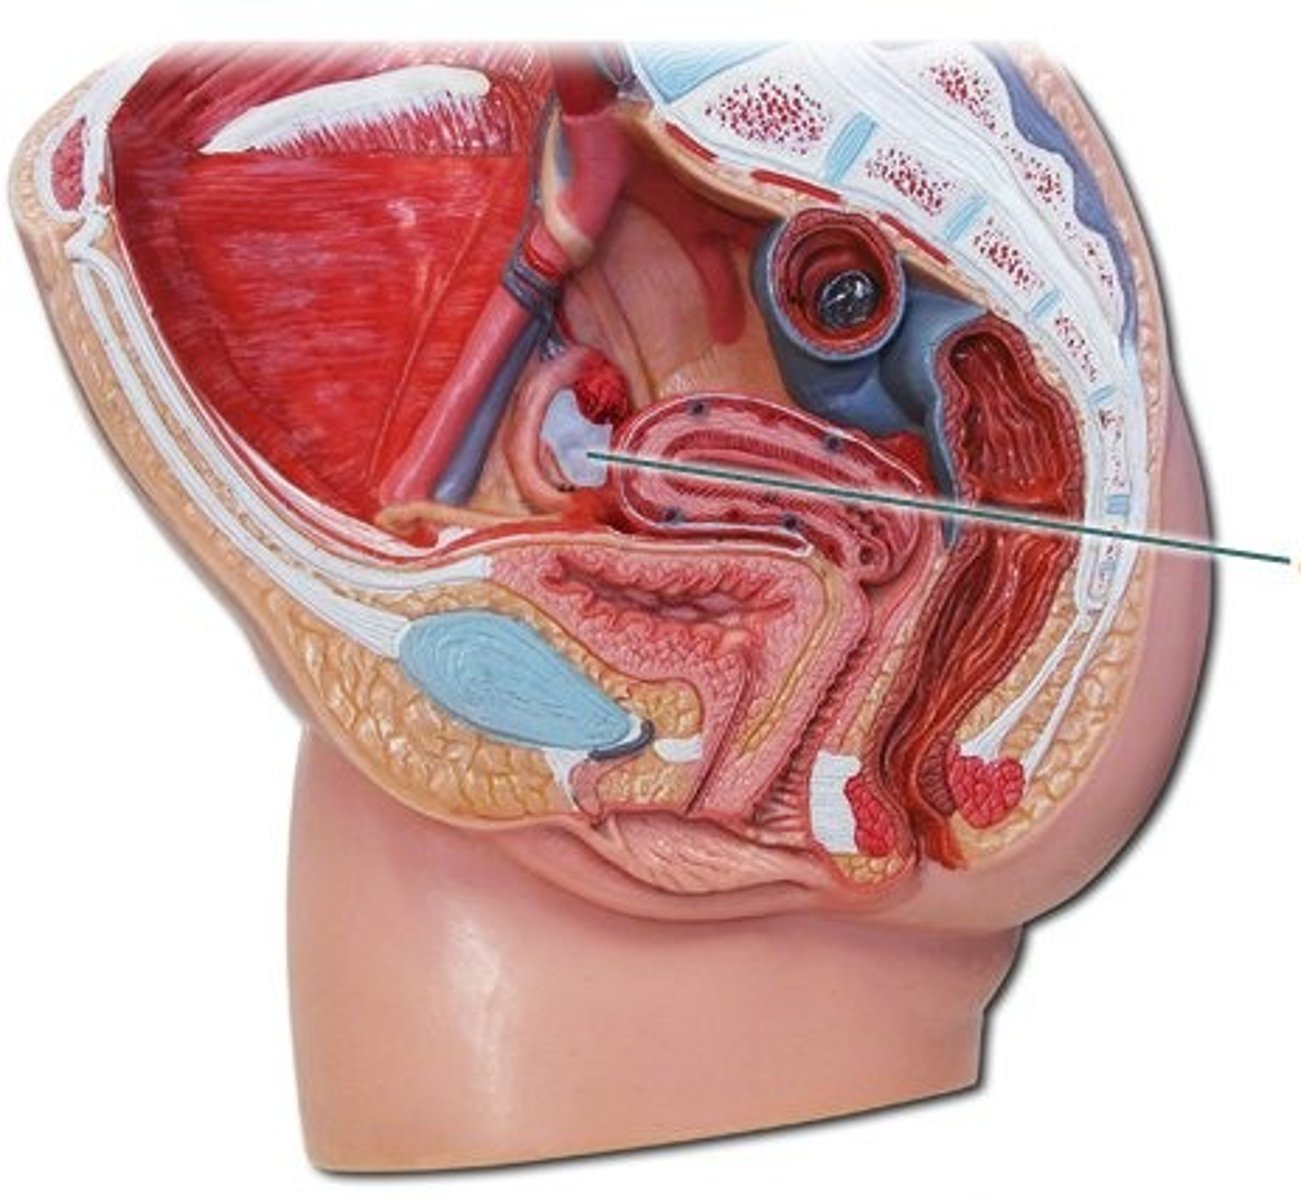

broad ligament

ovarian ligament

ovary

suspensory ligament

uterine tube

uterus

cervix

fundus